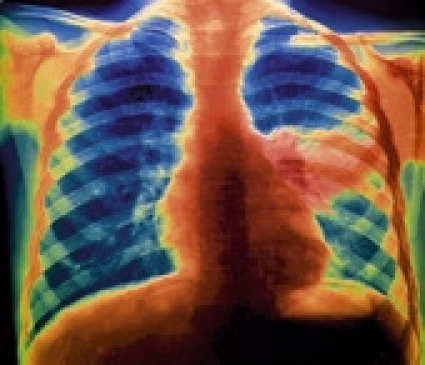

Den optimala antibiotikabehandlingen vid samhällsförvärvad pneumoni är oklar. Det beror bland annat på svårigheterna att ställa etiologisk diagnos. Det är också omdiskuterat i vilken utsträckning primär behandling av pneumoni, förutom för Streptococcus pneumoniae, också bör täcka atypiska patogener (Mycoplasma pneumoniae, Legionella spp och Chlamydophila pneumoniae).